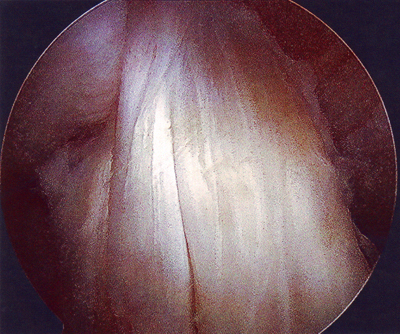

Moni miettii, miltäköhän tuon polven sisällä näyttää? Se selviää vilkaisemalla alla olevia kuvia!

Vasemmanpuoleinen kuva kertoo syvällä olleesta sisäkierukan repeämästä. Oikeanpuoleinen kuva on sisäreiden rustokulumasta, vaikka ei tämmöisellä hyvällä hevosella voi mitään kulumia olla!